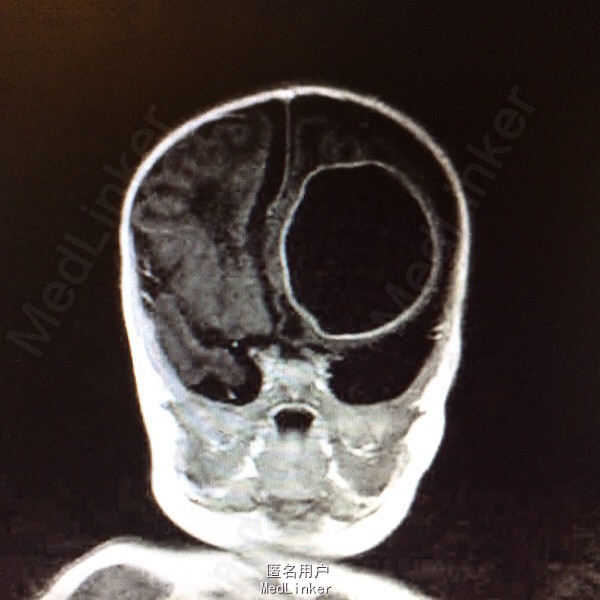

血常规:白细胞计数 WBC 18.61*10~9/L,中性粒细胞比例 Neu% 47.5%,淋巴细胞比例 Lym% 40.3%,血红蛋白 HGB 115g/L,血小板计数 PLT 433*10~9/L,CRP 79mg/L。大小便常规基本正常。肝肾功血糖心肌酶谱基本正常。降钙素原定量 PCT 1.80ng/ml。脑脊液生化 蛋白质 M-TP 528.1mg/灯笼,氯化物 CL 111.5mmol/L,葡萄糖 GLU 0.19mmol/L。 脑脊液常规检查(CSF) 细胞总数 110516.0×10~6/L,白细胞计数 108500.0×10~6/L,红细胞计数 2016×10~6/L,直接分类-单个核细胞比例 45%,直接分类-多核细胞比例 55%,颜色 黄色,透明度 浑浊,蛋白定性(Pandy's) 阳性(2+)。胸片:双肺改变考虑炎变,建议治疗后复查。颅内(彩超) :左侧脑实质囊性占位。磁共振增强扫描颅脑 :1、左侧额叶较大混杂信号囊状影,增强扫描壁明显强化,考虑脑脓肿;伴额、颞部蛛网膜下腔积液,请结合临床及其它检查。2、左侧侧脑室后角旁小结节影,增强扫描环形强化,考虑小脓肿可能。3、右侧侧脑室前角两处囊状影,未见强化,软化灶可能大,原因?PVL?